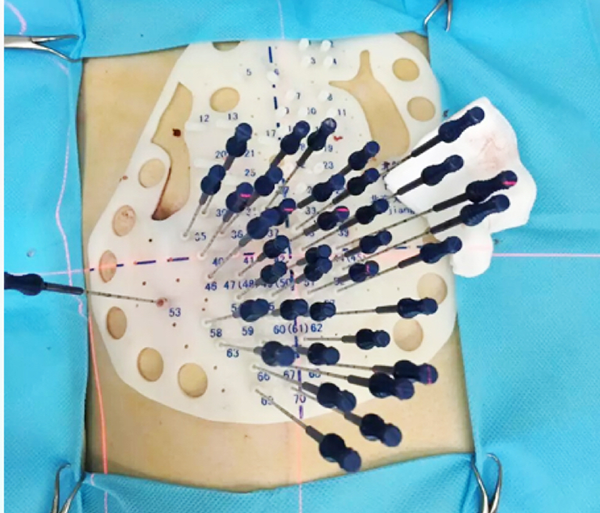

粒子植入室里的“精准刻度”:毫米间的生命希望

在碘125粒子植入手术室,核医学科的医生们正对着CT影像计算角度。“再往左偏0.5厘米,避开血管”,金子主任盯着屏幕,手里的穿刺针稳如雕塑。每一粒粒子都像精准投放的“生命种子”,要在肿瘤内部找到最佳靶位。

这是一位80岁的肺癌患者因无法耐受手术,选择了碘125粒子植入这种微创、安全、有效的局部治疗手段,核医学医生们反复模拟植入路径,连患者呼吸的频率都记在心里。手术时,患者突然咳嗽,医生立刻停手,轻声说:“深呼吸,我们等您。”当最后一粒粒子植入,他们用尺子再次核对位置,确保误差不超过1毫米。